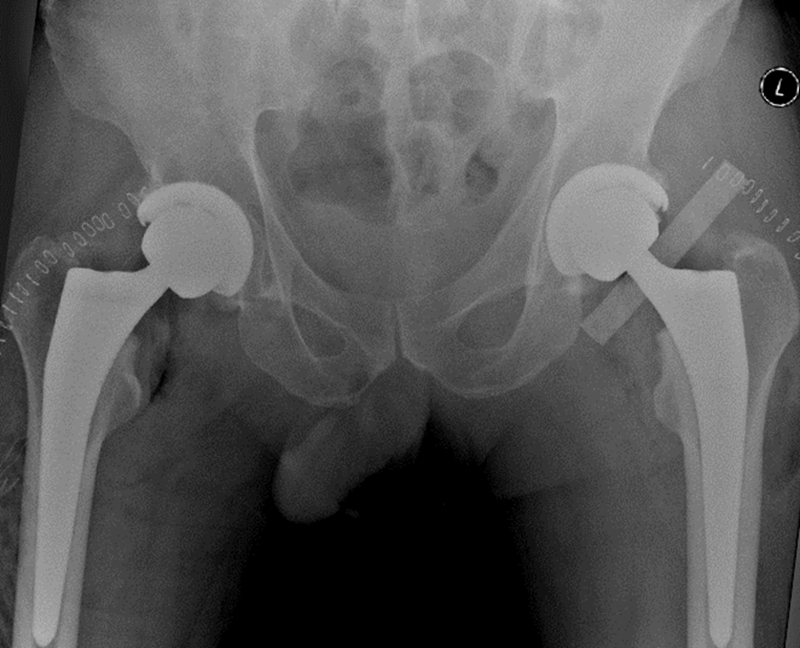

患者男性,48岁,诊断为“股骨头坏死”(图3),接受了VTS导航辅助下初次双侧全髋关节置换术,手术顺利,一侧手术仅用时约60分钟。术后影像学结果显示,假体位置、角度和肢体长度都非常满意(图4),次日患者即可下地活动,术后3日后即平稳出院。

图4 患者术后X光片,假体位置和角度理想,下肢偏心距和长度得到了重建